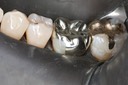

Scott Kanamori #31 pre-op

Scott Kanamori #31 amalgam removal